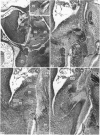

In this study, we analyse the process of spatial organisation of the cochlear root related to the morphological and topographical changes in the CN during the prenatal development of Wistar rats, placing special emphasis on aspects of the latero-medial distribution of the cochlear afferents. A total of 35 embryos from 8 Wistar rats was employed, corresponding to embryonic days 14, 16, 18 and 20. Twenty of these embryos were studied by the Cajal's reduced silver stain and 15 by the rapid Golgi method (osmium dichromate method). The otocyst, the vestibulo-cochlear ganglion and vestibulo-cochlear nerve were first observed at embryonic Day 14 (E14). At E16, a sharp separation between the cochlear and vestibular roots was distinguished. The final position of the primary afferents and their main branches (anterior and posterior) in the CN was observed at E18 and E20, when the total number of cochlear turns had been formed. The cochlear afferents coming from the apical coil, the last to be incorporated into the cochlear root, project their posterior branches at the bifurcation towards more medial portions of the PVCN and their anterior branches towards the more lateral regions of the AVCN.